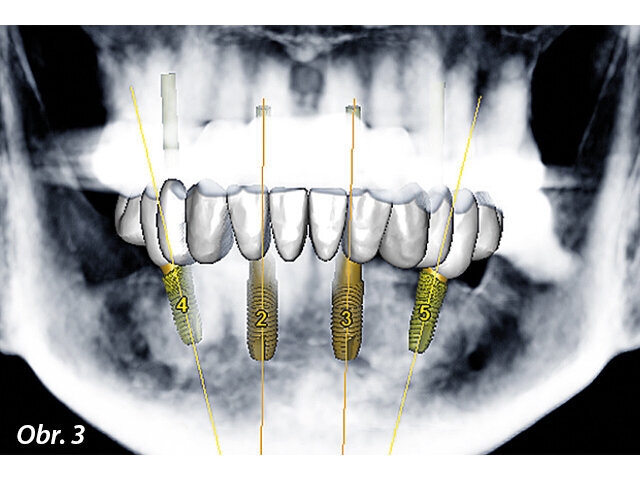

Pacientka si zvolila komplexní rehabilitaci chrupu v dolní čelisti fixní náhradou nesenou implantáty s využitím čtyř implantátů. Zbývajících pět zubů vykazovalo vhodný vertikální rozměr okluze v centrickém vztahu s okluzní rovinou poskytující přijatelnou fonetiku a estetiku (obr. 1). Byl pořízen panoramatický rentgenový snímek pro zaznamenání dentoalveolárního stavu v době, kdy se pacientka dostavila poprvé do ordinace (obr. 2). Předchozí selhávající distální fixní zubní náhrada byla odstraněna ještě před definitivním plánováním léčby.

Obr. 1: Intraorální vzhled stavu chrupu před ošetřením